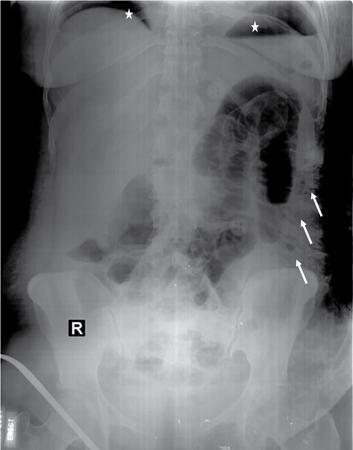

UNDERSTANDING THE ADULT ABDOMINAL RADIOGRAPH: TECHNIQUES AND INTERPRETATION Tanvi Modi Radiography of the abdomen is a common practice for the evaluation of abdominal organs. The anatomy and pathology of digestive, hepatobiliary and genitourinary systems can be assessed using radiographs, either as a stand-alone practice or as a primary imaging modality followed by contrast studies, ultrasound or cross-sectional imaging. In addition, abnormalities of the musculoskeletal or integumentary system can also be deduced on the basis of abdominal radiographs. This chapter intends to give an overview on the techniques and positioning in abdominal radiography as well as interpretation of normal and abnormal features. While superior imaging modalities such as ultrasound, computed tomography (CT), magnetic resonance imaging, capsule endoscopy and the likes have taken over abdominal imaging by and large, radiography still holds a pivotal role in certain situations and conditions, such as: The standard abdominal radiograph is taken in supine position and anteroposterior projection. This is also popularly known as the KUB (kidneys-ureters-bladder) radiograph. Previously, supine as well as erect radiographs were performed in all patients; however, this is not commonly done due to high-radiation dose. For all indications of abdominal radiography, including acute abdomen, supine radiographs are sufficient in terms of radiographic diagnosis, with the exception of perforation for which an erect chest or lateral decubitus radiograph can be performed if there is clinical suspicion. Patient should lie supine on the imaging table with median sagittal plane at right angles to the table and coincident with the midline of the table (Fig. 7.1.1.1). The body is divided into equal right and left halves by the median sagittal which passes through the sagittal suture of the skull. Pelvis should be adjusted so that the anterior superior iliac spines are equidistant from the table top. Gonadal shields, in the case of male patients, should be placed with the upper edge of the shield at the level of pubic symphysis. Although rarely used for female patients, these should be positioned between the anterior superior iliac spines and the pubic symphysis. The centre point of the image receptor should be approximately located at a point 1 cm below the line joining the iliac crests. The X-ray beam should be in a vertical direction, perpendicular to the table top and image receptor at the centre point. Collimation should be such that the soft tissue and subcutaneous region along lateral aspects of the abdominal cavity should be covered within the image. Also, the superior extent involving diaphragm and inferior extent involving the inferior pubic rami is important to look for any lower chest pathologies or any inguinal hernia. 35 × 43 cm (14 × 17 inches) in portrait orientation. On an average, abdominal radiograph exposes a patient to a dose of approximately 1.5 mSv, which is equivalent to 75 chest radiographs or 1/6th dose of a standard CT of the abdomen. The entrance skin dose is approximated to be 4 mGy. At such an effective dose, the additional lifetime risk of fatal cancer is 1 in 30,000. The exposure time is kept short. Patient is asked to exhale completely and hold their breath, with exposure taken at this point of full expiration to ensure imaging of abdominal organs in their natural positions. Modifications of this technique can be made depending on patient habitus and clinical condition. Kilovoltage peak (kVp) should be set to allow adequate visualization of abdominal soft tissue structures as well as semiopaque renal and biliary calculi. Average kVp is set at 70–85 kV. 102 cm (40 inches) Grids are commonly used to reduce scatter radiation. Placement of side marker on the image receptor at the time of radiographic exposure is essential. Bowel pattern depiction should be such that there is minimal lack of sharpness. Standard guidelines for abdominal radiography dictate that the radiograph should extend from the diaphragm up to the level of inferior pubic rami and must include the lateral abdominal wall musculature. The abdomen is divided into four quadrants on the basis of two perpendicular lines (Fig. 7.1.1.7). The vertical line passes through the mid sagittal plane and crosses the umbilicus and symphysis pubis. The horizontal line is a transverse line across the umbilicus at 90 degrees to the vertical line and is situated at the level of L4–L5 intervertebral disc. The quadrants are as follows: Another division system is dividing the abdominopelvic cavity into nine regions using two vertical and two horizontal planes (Fig. 7.1.1.8). The vertical planes, also known as the right and left lateral planes, are parallel to the midsagittal plane between midline and anterosuperior iliac spines on either side. Of the two horizontal planes, the upper transpyloric plane is at the level of lower border of L1 and the lower transtubercular plane is at the level of L5. The nine regions are: On a standard radiograph, the exposure should be such that the stomach, bowel loops, outlines of liver, spleen, kidneys, psoas muscles should be well identified. Also, lumbar transverse processes should be seen. Arch of the pubic symphysis should be visible to evaluate bladder region. A well-centred film without rotation will demonstrate bilaterally symmetrical lower ribs, iliac wings, ischial spines and obturator foramina. Different structures seen on an abdominal radiograph can be classified into five basic densities: Identification of different structures depends on the relative degree of contrast between their densities. The demarcation is clearer in chest and is diminished in abdomen due to relative similar soft tissue density of various structures. On a normal radiograph, relatively large amounts of gas in stomach and colon with minimal small bowel gas can be seen. Further, colonic gas can vary from negligible to extensive, mimicking obstruction pattern; however, usually the gas is enough to delineate colonic haustral pattern. Faecal matter gives a mottled appearance to colonic gas. Short-air fluid levels on an erect radiograph may be seen even in normal cases. The normal appearance of small bowel loops on an abdominal radiograph follows the rule of threes: Stomach is seen in the left upper quadrant and is visualized when distended with air. It is commonly seen extending from T11 to L2 level. Common feature identifying the stomach is the fundal gas which is usually seen as an air fluid level within the gastric lumen. Small bowel loops are distributed to the centre of the abdominal cavity and large bowel loops are peripheral. Duodenum is predominantly situated in right upper quadrant. It extends to left upper quadrant in the region of duodenojejunal flexure. Jejunum occupies the left upper and lower quadrants and is easily identified due to the presence of thick, numerous, closely spaced valvulae conniventes (Fig. 7.1.1.9A). The ileum occupies both lower quadrants and extends into right upper quadrant. Ileum has few and less prominent valvulae as compared to jejunum (Fig. 7.1.1.9B). Ascending and descending colon are retroperitoneal and have relatively fixed positions along lateral aspect of the abdominal cavity on either side. Transverse and sigmoid colon, on the other hand, may have a variable position due to their mobility along mesocolon and redundant pattern. These can be identified with confidence on account of haustrations and faecal matter (Fig. 7.1.1.10). Haustrations are usually well seen in ascending and transverse colon and poorly delineated beyond splenic flexure. Caecum is in the right lower quadrant, though it may be mobile or pulled up. Rectal gas is usually seen in the midline at the level of pelvis and its presence rules out large bowel obstruction. All these positions may vary due to anatomical conditions such as malrotation or pathological conditions, for example volvulus. Liver, spleen and renal outlines cannot be completely traced with precision due to the overlap by bowel loops. On a frontal projection, the liver appears as a triangular structure occupying right and left hypochondrium and epigastric region. Occasionally, the right lobe may be seen extending lower than the right renal shadow. This is a normal variant known as Reidel’s lobe. Gall bladder is situated in the posterior and inferior region of the liver and any pathology of the gall bladder should be looked for in this region. On a lateral radiograph, the gall bladder is anterior to the midcoronal plane. This helps in distinguishing gall bladder calculi from renal calculi, which will be more posteriorly situated. Spleen is seen in left upper quadrant/left hypochondrium, flushed to left lower ribs and left hemidiaphragm. Pancreas is present in the epigastric region (right and left upper quadrants) and is usually not identified in the absence of a pathology. The kidneys are bean-shaped retroperitoneal organs which are seen on either side of the vertebral column and lateral to psoas muscles. Due to the presence of liver on the right side, this kidney is slightly lower in position as compared to its contralateral counterpart. The visualization of kidneys on radiographs is facilitated by the surrounding fatty capsule. Kidneys lie between T11–12 and L2 level, with left kidney 1 cm higher than the right. Psoas muscle shadow can be normally seen along lateral aspect of lumbar spine bilaterally and is mildly concave (Fig. 7.1.1.11). Abdominal wall muscles are not routinely assessed on radiography; however, inclusion of lateral abdominal wall (muscles as well as subcutaneous plane) is a must while performing radiography. The flank stripe or the properitoneal fat stripe is a fat density linear concavity seen along lateral abdominal wall (Fig. 7.1.1.11). It is bound by the paracolic gutters and air-filled ascending and descending colon. All the solid organs in the abdomen are identified due to the fat density outlining them. Distortion of these fat lines helps in identifying organomegaly or focal mass lesions. The dome of urinary bladder is outlined by fat, which aids in differentiating its density from other soft tissue structures of the pelvis. Not all calcifications seen on abdominal radiograph are abnormal. Some may depict age-related changes such as vascular calcifications involving abdominal aorta, pelvic vessels, splenic artery in the region of left upper quadrant. Within the pelvis, phleboliths may be seen and mistaken for urinary calculi. Assessment of lumbosacral spine, iliac bones and femoral heads can be made on the basis of plain radiography. Degenerative changes may be commonly seen. Lower ribs can also be evaluated for pathologies. Dilated small bowel loops with rounded soft tissue density in midline over umbilical region suggests obstruction secondary to umbilical hernia. Pneumoperitoneum must be looked for in all cases of acute abdomen. While erect chest and left lateral decubitus radiographs can detect even 1 mL of free air, there are multiple signs on supine radiograph to suggest this diagnosis, for example Rigler’s sign, falciform ligament sign, football sign (Figs. 7.1.1.24 and 7.1.1.25). Retroperitoneal perforation may demonstrate air outlining psoas muscles and retroperitoneal organs. Small amount of free air may persist in the abdominal cavity up to 3 weeks after surgery, although it usually resolves within a week. Clinical history is important in such cases. Air foci within the bowel wall may represent bowel ischaemia/strangulation. Linear gas patterns in right hypochondrium may be due to two causes, that is pneumobilia and pneumoporta. The former can be seen normally postbiliary surgery, sphincterotomy, ERCP or in the case of abnormal fistulous communication between bowel and biliary tree (Fig. 7.1.1.26A). Pneumoporta (Fig. 7.1.1.26B) is a red flag and warrants further investigation to look for conditions such as mesenteric ischaemia and toxic megacolon. Pneumobilia is more centrally located whereas air shadows in pneumoporta are seen reaching up to periphery of liver. Air foci over renal shadows (Fig. 7.1.1.27), gall bladder or pancreas, in the absence of recent procedural history, suggest fulminant infection and mandate urgent intervention. Central midline calcific foci between T9 and T12 vertebrae can be attributed to calcific pancreatitis (Fig. 7.1.1.28). In the left upper quadrant, areas of calcification seen involving a shrunken spleen may be seen in autosplenectomy. In right upper quadrant, calcified gall stones may be seen. These tend to be small, multiple, uniformly circumscribed and ring-like in appearance with central translucency (Fig. 7.1.1.29A). Mercedes Benz sign, a triradiate pattern of gas lucency, is associated with gallstones. In contrast, renal calculi are more commonly solitary, irregular, of homogenous density, conform to renal calyceal or pelvic outline (Fig. 7.1.1.29B) and are sometimes of staghorn configuration. On lateral view, the gall stones are more anteriorly located as compared to renal calculi, which may be partly superimposed on lumbar vertebrae. Ureteric calculi tend to overlap bony structures such as lumbar transverse processes (Fig. 7.1.1.29B) or sacroiliac joints. Extensive or patchy, curvilinear calcification of gall bladder wall is known as porcelain gall bladder which is often associated with malignant transformation. Calcification involving adrenal glands may be secondary to infection or haematoma, or a congenital condition known as Wolman’s disease where there is bilateral involvement. Discontinuous discrete midline tram track calcification in the abdomen may indicate atherosclerotic changes in abdominal aorta and branch vessels. However, when the calcification is in a globular pattern and seen below the level of L2 vertebra, aortic aneurysm should be suspected (Fig. 7.1.1.30). Appendicoliths, though not commonly seen, may sometimes be detected in right iliac region. Pelvic calcifications: vesical calculi, distal ureteric or vesicoureteric junction calculi, calcified fibroids, ovarian dermoid with tooth-like calcifications (Fig. 7.1.1.31) may be the cause of abdominal pain and should be diligently looked for. Vesical calculi are usually more large and central in location whereas calcification due to fibroids may be more lateral. Schistosomiasis is another cause of bladder wall calcification, as is calcification of bladder tumours. Phleboliths tend to be bilaterally symmetrical, with a lucent centre unlike ureteric calculi. While it is believed that phleboliths are located below the level of ischial spines and ureteric calculi above, this is not always true and should be confirmed with CT. Fluid may collect adjacent to properitoneal fat line, forming a linear soft tissue density separating the fat line from the ascending or descending colon. Hellmer’s sign demonstrates medial displacement of lateral edge of liver (hepatic angle), due to fluid collection or ascites. Gross ascites may appear as generalized abdominal haziness or diffuse increased density of pelvis. Abscesses can involve any solid organ and in such cases may be difficult to demonstrate on plain radiography alone. Enlargement of organ or faint gas densities within can be suggestive of the same. In the case of peritoneal abscess, mottled density due to air, fluid and necrotic contents point towards this diagnosis, especially in right iliac fossa in association with appendicitis. Retroperitoneal abscess, similar to any retroperitoneal mass, may cause displacement of retroperitoneal structures (Fig. 7.1.1.32). Subdiaphragmatic abscesses may show concomitant ipsilateral pleural effusion (Fig. 7.1.1.33). These should be differentiated from Chilaiditi syndrome. Fluid and soft tissue lesions present with the same density on radiographs. While it is difficult to characterize the lesion and organ of origin, clues for the same can be provided by organomegaly (Fig. 7.1.1.34), distortion of fat surrounding solid organs, displacement of bowel loops or solid organs. For example, a retroperitoneal lesion may cause anterior or inferior displacement of kidney, a pelvic mass may cause upward displacement of small bowel loops. Different densities such as fat or calcification may help in identifying organ of origin (e.g. fat and tooth densities seen in ovarian dermoid). Convexity of margins of psoas muscle on an abdominal radiograph can be due to haematoma, abscess or intramuscular tumour. Radiographs are performed for the initial diagnosis of foreign body in the abdomen including type, number of foreign bodies, location, size and shape (Fig. 7.1.1.35). Radiolucent foreign bodies such as wood, plastic, chicken bones will not be easily identified on radiography. Low kVp (65–70 kVp) can increase contrast and help identify these objects. In addition to an abdominal radiograph, chest radiography is also performed to exclude aspiration or oesophageal location of foreign body. Ingested or introduced foreign bodies may cause complications such as obstruction, perforation, fistula formation and sepsis. Hence, once their presence is confirmed, follow up radiography must be performed until they are eliminated. One must look for fractures/dislocation injuries involving the vertebrae or pelvic bones, especially after history of trauma. Lucent expansile lesions or sclerotic bony deposits which represent neoplasms, absent pedicle sign in cases of metastasis, metabolic bony changes such as rugger jersey appearance, Paget’s disease, arthropathies such as ankylosing spondylitis with bamboo spine appearance and sacroiliitis (Fig. 7.1.1.36) are some of the conditions which may be diagnosed based on an abdominal radiograph. Overlap of bowel loops over iliac blades may lead to a misdiagnosis of lucent lesions and should be evaluated with caution. Basal pneumonia may be the cause of acute abdominal pain and should be looked for in abdominal radiography. Similarly, pleural effusion, pericardial effusion, calcified pleural plaques, achalasia, interstitial fibrosis are few other findings that can be seen in lower chest on an abdominal radiograph. Basilar atelectasis can give a deceptive appearance of pneumoperitoneum (Fig. 7.1.1.37). Surgical clips, commonly in right hypochondrium after cholecystectomy, drainage tubes, ventriculoperitoneal shunts, femoral line catheters, IVC filters, stents (vascular, renal, biliary) (Fig. 7.1.1.38), stoma bags, contraceptive devices are some structures that may be seen in an abdominal radiograph. Correct knowledge of patient history and normal locations of these structures prevents misdiagnosis. Certain artefacts may be projected upon the radiograph due to surface structures such as trouser buttons, body piercing, sequins over clothing and should not be considered as a pathology. Multiple skin surface nodules in cases of neurofibromatosis, soft tissue focal swellings, such as abscesses, lipomas, haematomas, desmoid tumours and malignant lesions may be incidentally seen on radiography. These can be further evaluated using ultrasound or CT. Subcutaneous emphysema is another finding that may be seen in lower abdominal wall secondary to retroperitoneal perforation or diffusely along abdominal wall in the case of bowel perforation (Fig. 7.1.1.39). Foreign bodies such as bullets and pins may be seen lodged in abdominal wall. A systematic approach to abdominal radiographs is important for accurate diagnosis as follows: Despite the development of newer techniques for imaging of the abdomen, plain radiography still holds an important place in the initial assessment of acute abdomen. Positive and negative findings on an abdominal radiograph can direct further investigation. Ideal positioning, recognition of normal appearances and keen scrutiny for pathologies is a sine qua non for radiologists reading a plain film of the abdomen. OESOPHAGOGRAM Padma V. Badhe, Vikram Reddy, Sultan Moinuddin Shaukatali, Zillani Alam, Ravi Varma, Abhishek Bairy, Dasari Ravikiran, Revati Tekwani, Soniya Patankar, Megha Nair, Gautham Shankar Oesophagogram is the process of obtaining radiological images and simultaneous motion recording to evaluate function and disorders of pharynx, oesophagus and proximal stomach. Oesophagogram is usually done primarily to evaluate dysphagia. Some of the common indications are oesophageal motility disorders, strictures, gastro-oesophageal reflux disease (GERD) and suspected masses. It can also be used to detect uncommon anomalies like vascular rings/slings and aberrant anatomy. It also helps to evaluate further in cases where there is inability to pass upper GI scope. Double-contrast oesophagogram is mainly indicated in early mucosal disease like erosion, polyp, infection and tumours. If a motility disorder is suspected, dynamic technique (e.g. videofluoroscopy) is used for dysphagia or aspirations in cases of stroke, neuromuscular disorders, post head and neck surgery or radiation. Barium oesophagogram is contraindicated in suspected cases of perforation and tracheoesophageal fistula, aspiration, rarely if there is hypersensitivity to barium suspensions. It is also contraindicated in suspected oesophageal perforation where a water-soluble contrast agent is more suitable. However, ionic water-soluble contrast agent is better avoided in cases of aspiration or fistula with airway. The contrast examination of the pharynx is dangerous in cases of acute epiglottitis and must be ruled out on plain radiograph. An 80% w/v barium suspension is used in full column views. However, 200%–250% w/v barium suspensions is usually required for mucosal relief films. The barium sulphate mixture is fed to the patient either by spoon, by glass, or through a drinking straw, depending on its consistency. In videofluoroscopy, the pharyngeal phase of swallowing is usually safer with barium pudding than with thick barium and safer with thick barium than with thin barium. However, if the major abnormality is poor pharyngeal contraction leading to stasis in the piriform sinus (and epiglottic tilt is normal), a thin liquid is safer. Epiglottic motility is better assessed with thin barium because thick barium often obscures the epiglottic tip. Fluoroscopic equipment capable of cine fluoroscopy and capability for rapid sequence spot images (high frame rate) is needed for this examination, Barium suspension, straw, glass, Lead apron and radiation protective equipment. The patients are instructed to fast after midnight before the day of the examination. The pharynx should be made as dry as possible during the examination as high-density barium adheres to dry pharyngeal mucosa. Activities like smoking, chewing gum and lozenges must be abstained before the procedure as they impair barium coating by increasing the salivary secretion. Regular oral medications must be taken with sips of water; however, insulin must be skipped on the morning of examination. The major principles of a good oesophagogram includes mucosal coating, distension and projection. A routine oesophagogram consists of screening of the oral, pharyngeal and oesophageal phases of swallowing, single and double-contrast examination of pharynx, single contrast, double-contrast and mucosal relief views of the oesophagus. In cases of dysphagia, the examination is tailored depending on whether the symptoms are either pharyngeal or oesophageal and initial fluoroscopic findings. If patients’ symptoms are suggestive of oral or pharyngeal disorder then pharynx is evaluated first. Similarly, if patient is suspected to have thoracic oesophageal disease then, double-contrast examination of the oesophagus is performed before the pharyngeal evaluation. During an oesophagogram the positioning of the patient varies according to the type of examination (Table 7.1.2.1).